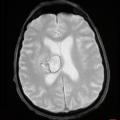

Hématome intracérébral profond

ACCIDENT VASCULAIRE CEREBRAL